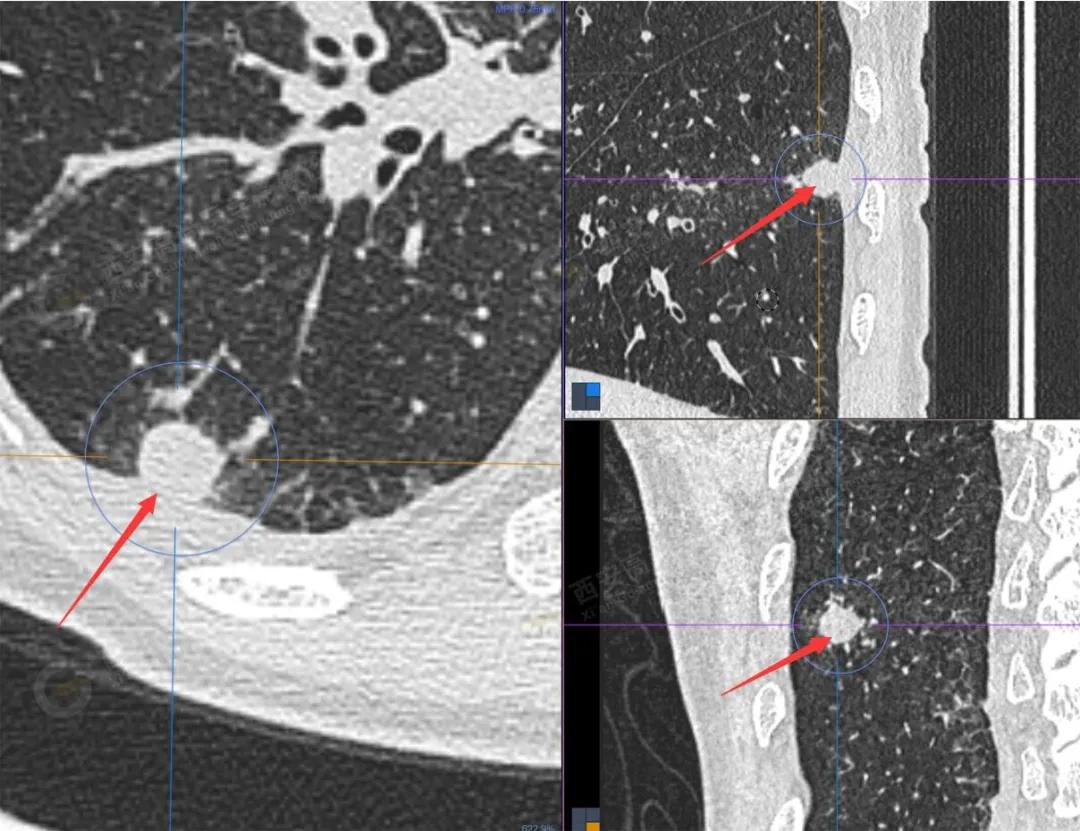

1.以下为肺内原发灶

原发病灶

FDG代谢增高

1.右肺下叶后基底段软组织结节(约1.5cm×1.2cm),与相邻后胸膜分界不清,呈FDG代谢异常增高,结合病理,符合肺腺癌伴邻近胸膜侵犯。